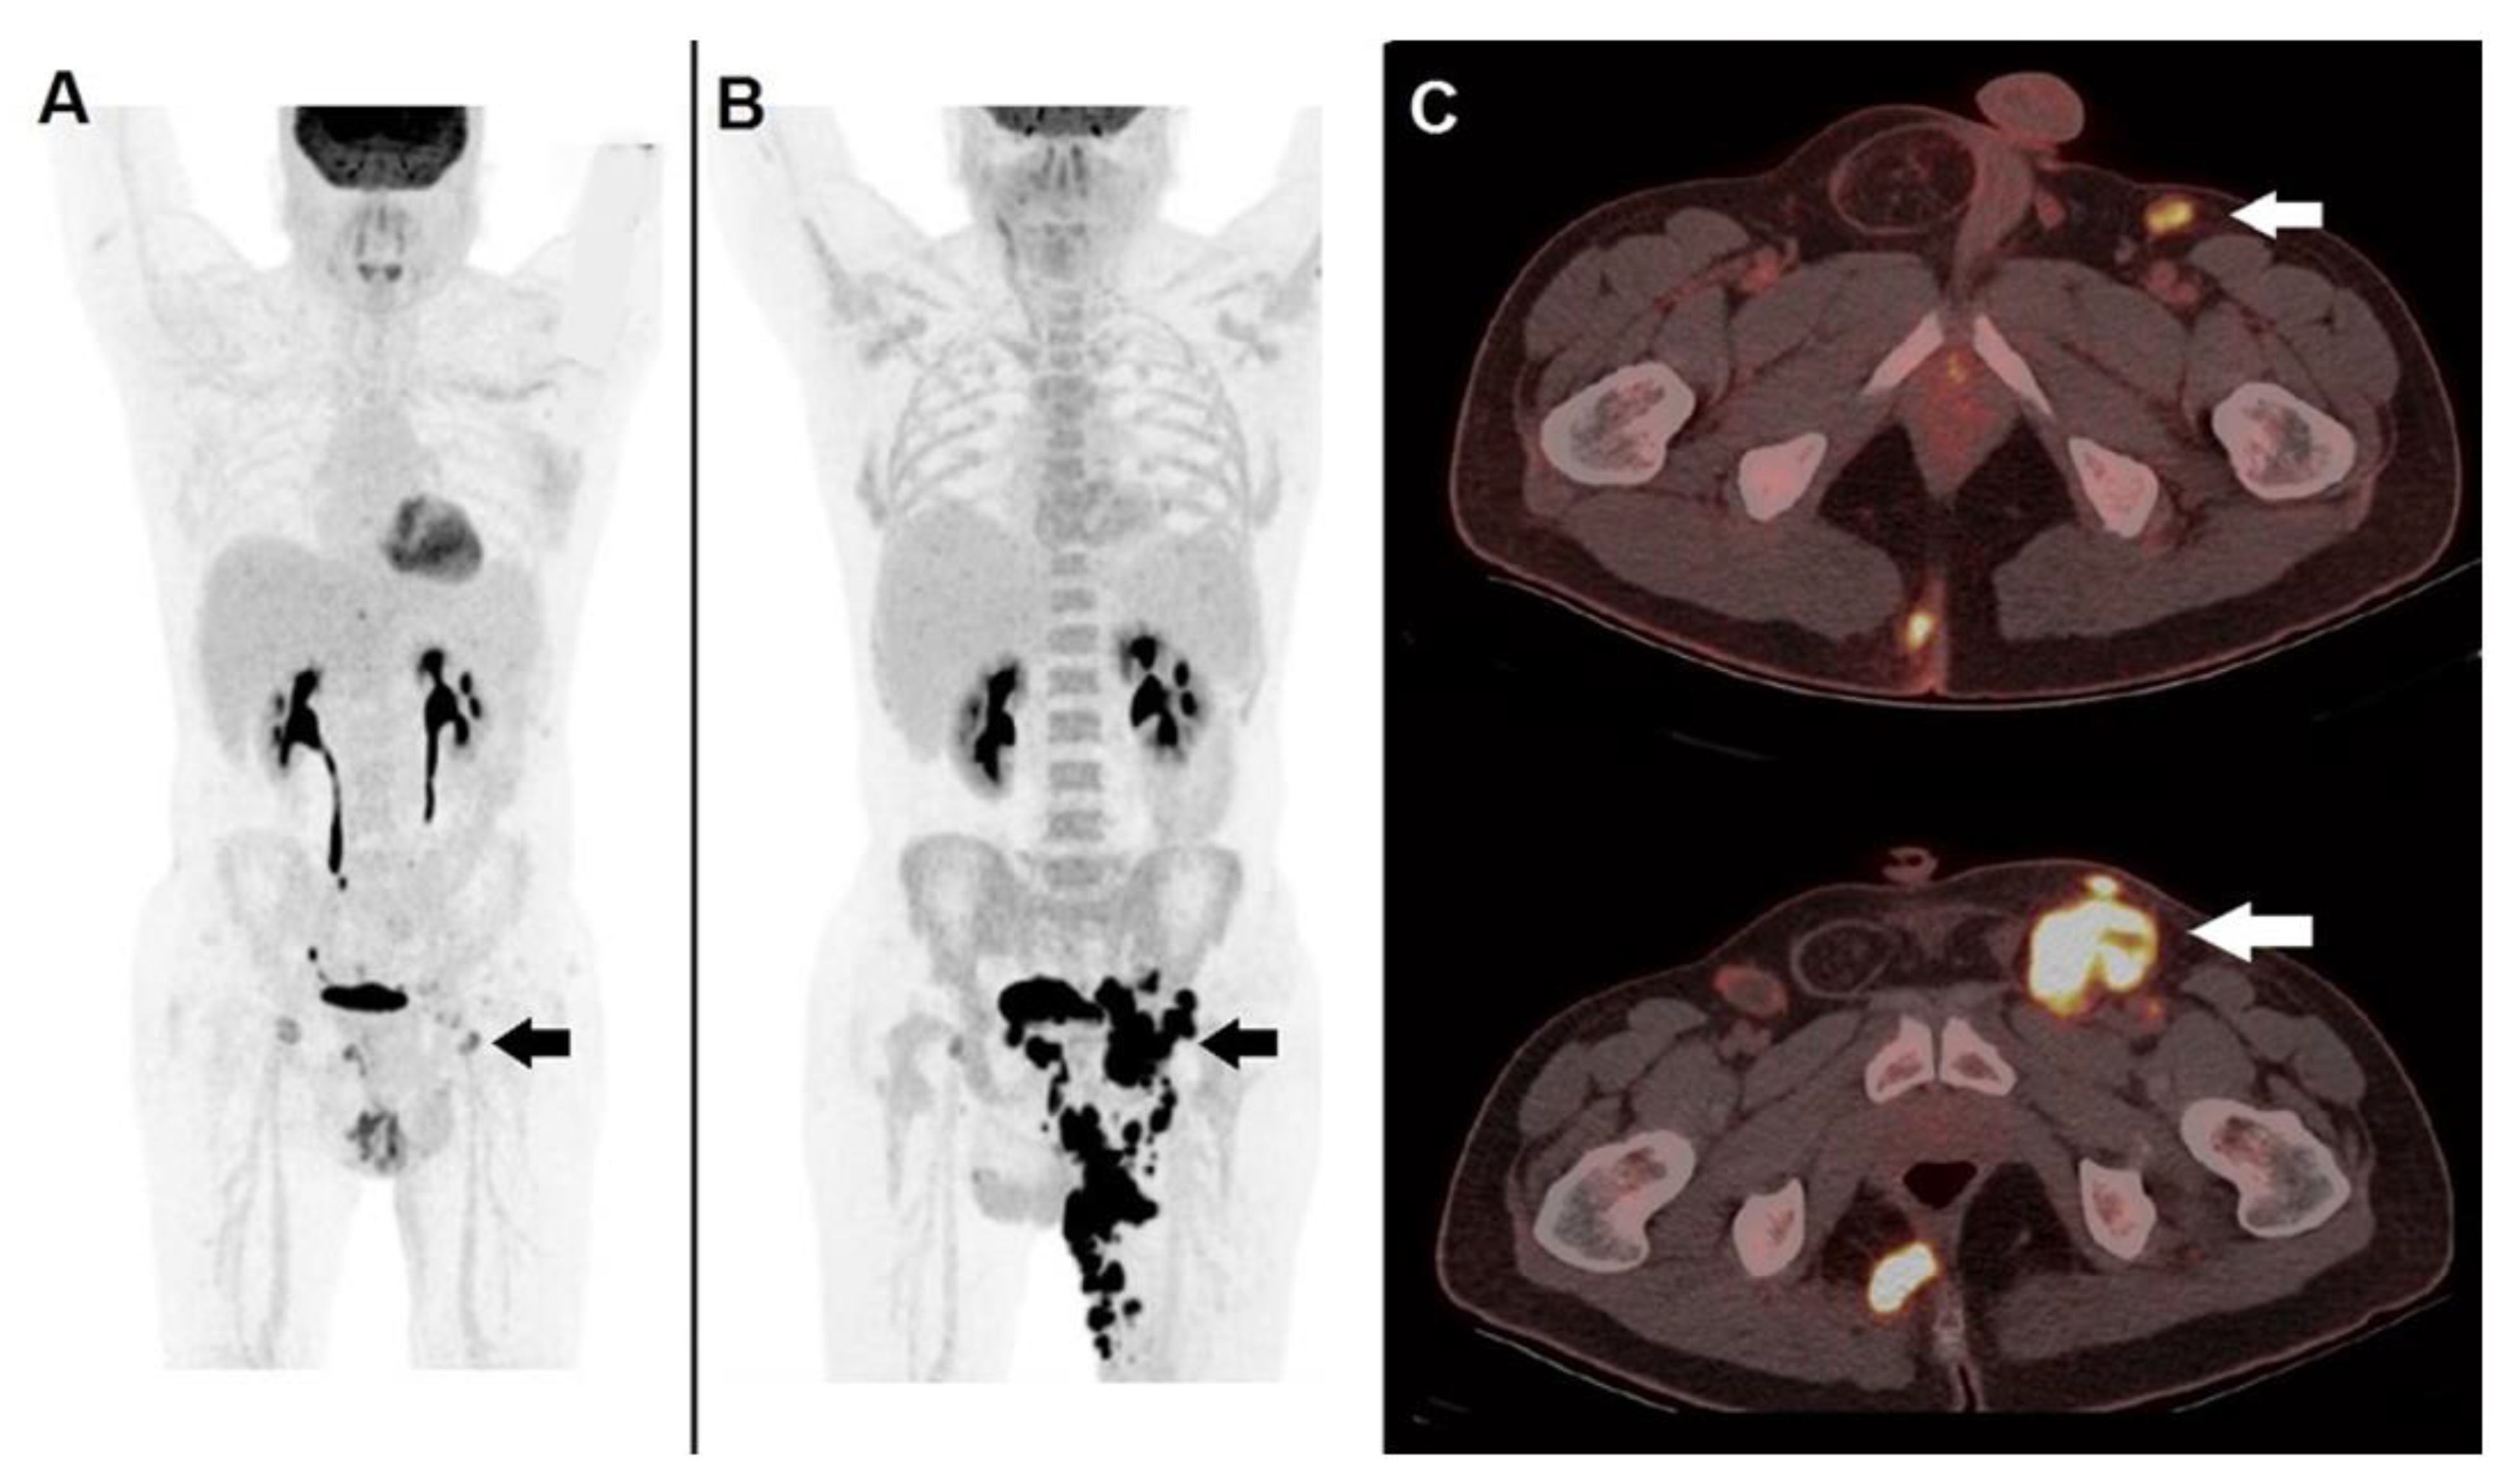

- Wahl, R.L.; Jacene, H.; Kasamon, Y.; Lodge, M.A. From RECIST to PERCIST: Evolving Considerations for PET Response Criteria in Solid Tumors. J. Nucl. Med. 2009, 50, 122S–150S. [Google Scholar] [CrossRef]

- Sachpekidis, C.; Larribere, L.; Pan, L.; Haberkorn, U.; Dimitrakopoulou-Strauss, A.; Hassel, J.C. Predictive Value of Early 18F-FDG PET/CT Studies for Treatment Response Evaluation to Ipilimumab in Metastatic Melanoma: Preliminary Results of an Ongoing Study. Eur. J. Nucl. Med. Mol. Imaging 2015, 42, 386–396. [Google Scholar] [CrossRef]

- Anwar, H.; Sachpekidis, C.; Winkler, J.; Kopp-Schneider, A.; Haberkorn, U.; Hassel, J.C.; Dimitrakopoulou-Strauss, A. Absolute Number of New Lesions on 18F-FDG PET/CT Is More Predictive of Clinical Response than SUV Changes in Metastatic Melanoma Patients Receiving Ipilimumab. Eur. J. Nucl Med. Mol. Imaging 2018, 45, 376–383. [Google Scholar] [CrossRef]

- Ito, K.; Teng, R.; Schöder, H.; Humm, J.L.; Ni, A.; Michaud, L.; Nakajima, R.; Yamashita, R.; Wolchok, J.D.; Weber, W.A. 18F-FDG PET/CT for Monitoring of Ipilimumab Therapy in Patients with Metastatic Melanoma. J. Nucl. Med. 2019, 60, 335–341. [Google Scholar] [CrossRef] [PubMed]

| Wahl et al. [47] | 2009 | PERCIST | Complete regression of all 18F-FDG-avid sites | SULpeak reduction in at least 30% in the target lesions | Increase in SULpeak of at least 30% or new lesions | None of the previously mentioned conditions |

| Sachpekidis et al. [48] | 2015 | EORTC | Complete regression of all 18F-FDG-avid sites | Minimum reduction of ±15–25% in SUV after the 1st cycle of chemotherapy, and >25% after more than one cycle | Increased SUVmax of ≥25% or appearance of new lesions | None of the previously mentioned conditions |

| Anwar et al. [49] | 2018 | PERCIMT | No new lesions (Clinical Benefit) | No new lesions (Clinical Benefit) | >4 new lesions with functional DM <1 cm, or three new lesions with functional diameter >1 cm or two new lesions with functional diameter >1.5 cm | None of the previously mentioned conditions |

| Goldfarb et al. [50] Filippi et al. [51] | 2019 2022 | iPERCIST | Complete regression of all 18F-FDG-avid sites | SULpeak reduction of at least 30% in the target lesions | Increase in SULpeak of at least 30% or new lesions (unconfirmed progressive disease/UPMD), needing confirmation (cPMD) with a further scan after 4–8 weeks. | None of the previously mentioned conditions |

| Ito et al. [52] | 2019 | Immunotherapy-modified PERCIST (imPERCIST5) | Complete regression of all 18F-FDG-avid sites | Sum of SULpeak decreased by at least 30% | Increase in the sum of SULpeak by at least 30% | None of the previously mentioned conditions |